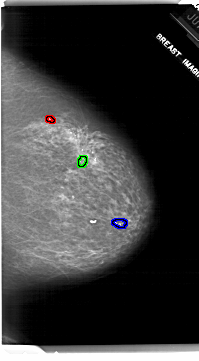

FILE: A_1917_1.RIGHT_MLO.OVERLAY

TOTAL_ABNORMALITIES 1

ABNORMALITY 1

LESION_TYPE CALCIFICATION TYPE DYSTROPHIC DISTRIBUTION CLUSTERED

ASSESSMENT 3

SUBTLETY 4

PATHOLOGY BENIGN

TOTAL_OUTLINES 1

ABNORMALITY 2

ABNORMALITY 3